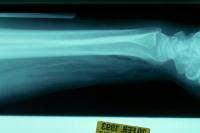

Forearm gas following multiple dog bites, but from injury, not gas forming infection - a diagnosis of exclusion: